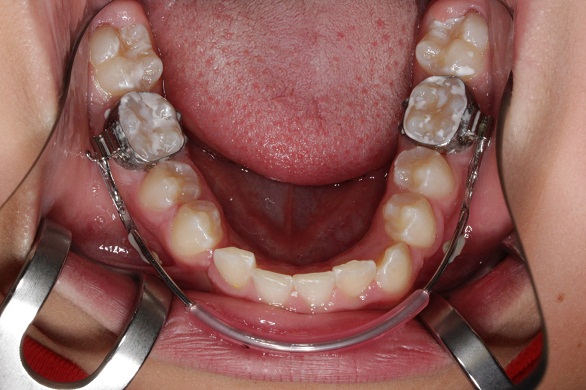

Lipbumper

Beim Lipbumper wird ein Innenbogen in der Umschlagfalte des Unterkiefers über Bänder gehalten. Er soll durch den Lippendruck der mimischen Muskulatur einen Mesialdrift der UK Molaren verhindern um somit zu einer Platzbeschaffung führen.